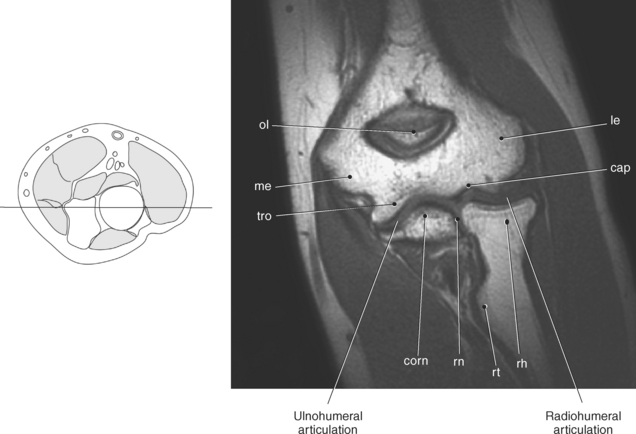

Figure 9.71 Coronal T1-weighted MR scan of elbow.

Key: ol, Olecranon fossa; me, medial epicondyle; tro, trochlea; le, lateral epicondyle; cap, capitellum; rh, radial head; rt, radial tuberosity; rn, radial notch; corn, coronoid process.

The distal portion of the humerus has two distinct prominences termed the medial and lateral condyles, with associated epicondyles, that provide attachment sites for tendons and ligaments (Figure 9.70). The medial epicondyle serves as the site of origin for the common flexor tendon, pronator teres muscle, and medial collateral ligament, whereas the lateral epicondyle serves as the attachment site for the common extensor tendon, supinator muscle, and lateral collateral ligament. Just lateral to the medial epicondyle along its posterior surface is a shallow groove containing the ulnar nerve. Two depressions located on the distal humerus are the anterior coronoid fossa and the deep posterior olecranon fossa. These depressions accommodate the coronoid and olecranon processes of the proximal ulna (Figures 9.70, 9.71, and 9.73). The distal humerus has two cartilage-covered articular surfaces—the capitellum and the trochlea for articulation with the radius and ulna (Figure 9.71). The lateral of the two surfaces is the capitellum, a rounded projection that articulates with the concave surface of the radial head. The trochlea is more medial and has the appearance of an hourglass if viewed in the horizontal plane. The shape of the trochlea helps keep the ulna in position during flexion between the distal humerus and proximal radius (Figure 9.73).